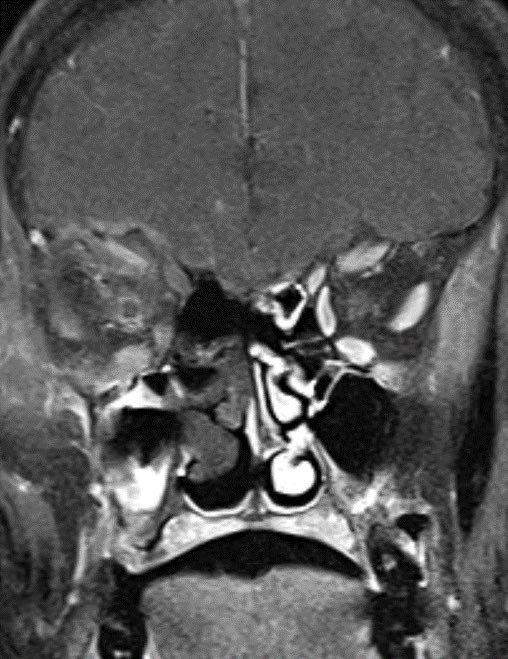

60 y/o with history of diabetes presents with progressive right proptosis, vision loss and confusion. What is the most likely diagnosis? 🧠

💡 Black Turbinate Sign has been reported as a finding highly suggestive of invasive fungal rhinosinusitis in immunocompromised patients

💡 Absent sinus mucosal enhancement is a 🔑 imaging feature as it implies invasion with vascular compromise and necrosis of the mucosa

💡 We must look for extra sinus invasion, particular intracranially, intraorbital, retromaxillary and other areas of absent mucosal enhancement to aid in the diagnosis